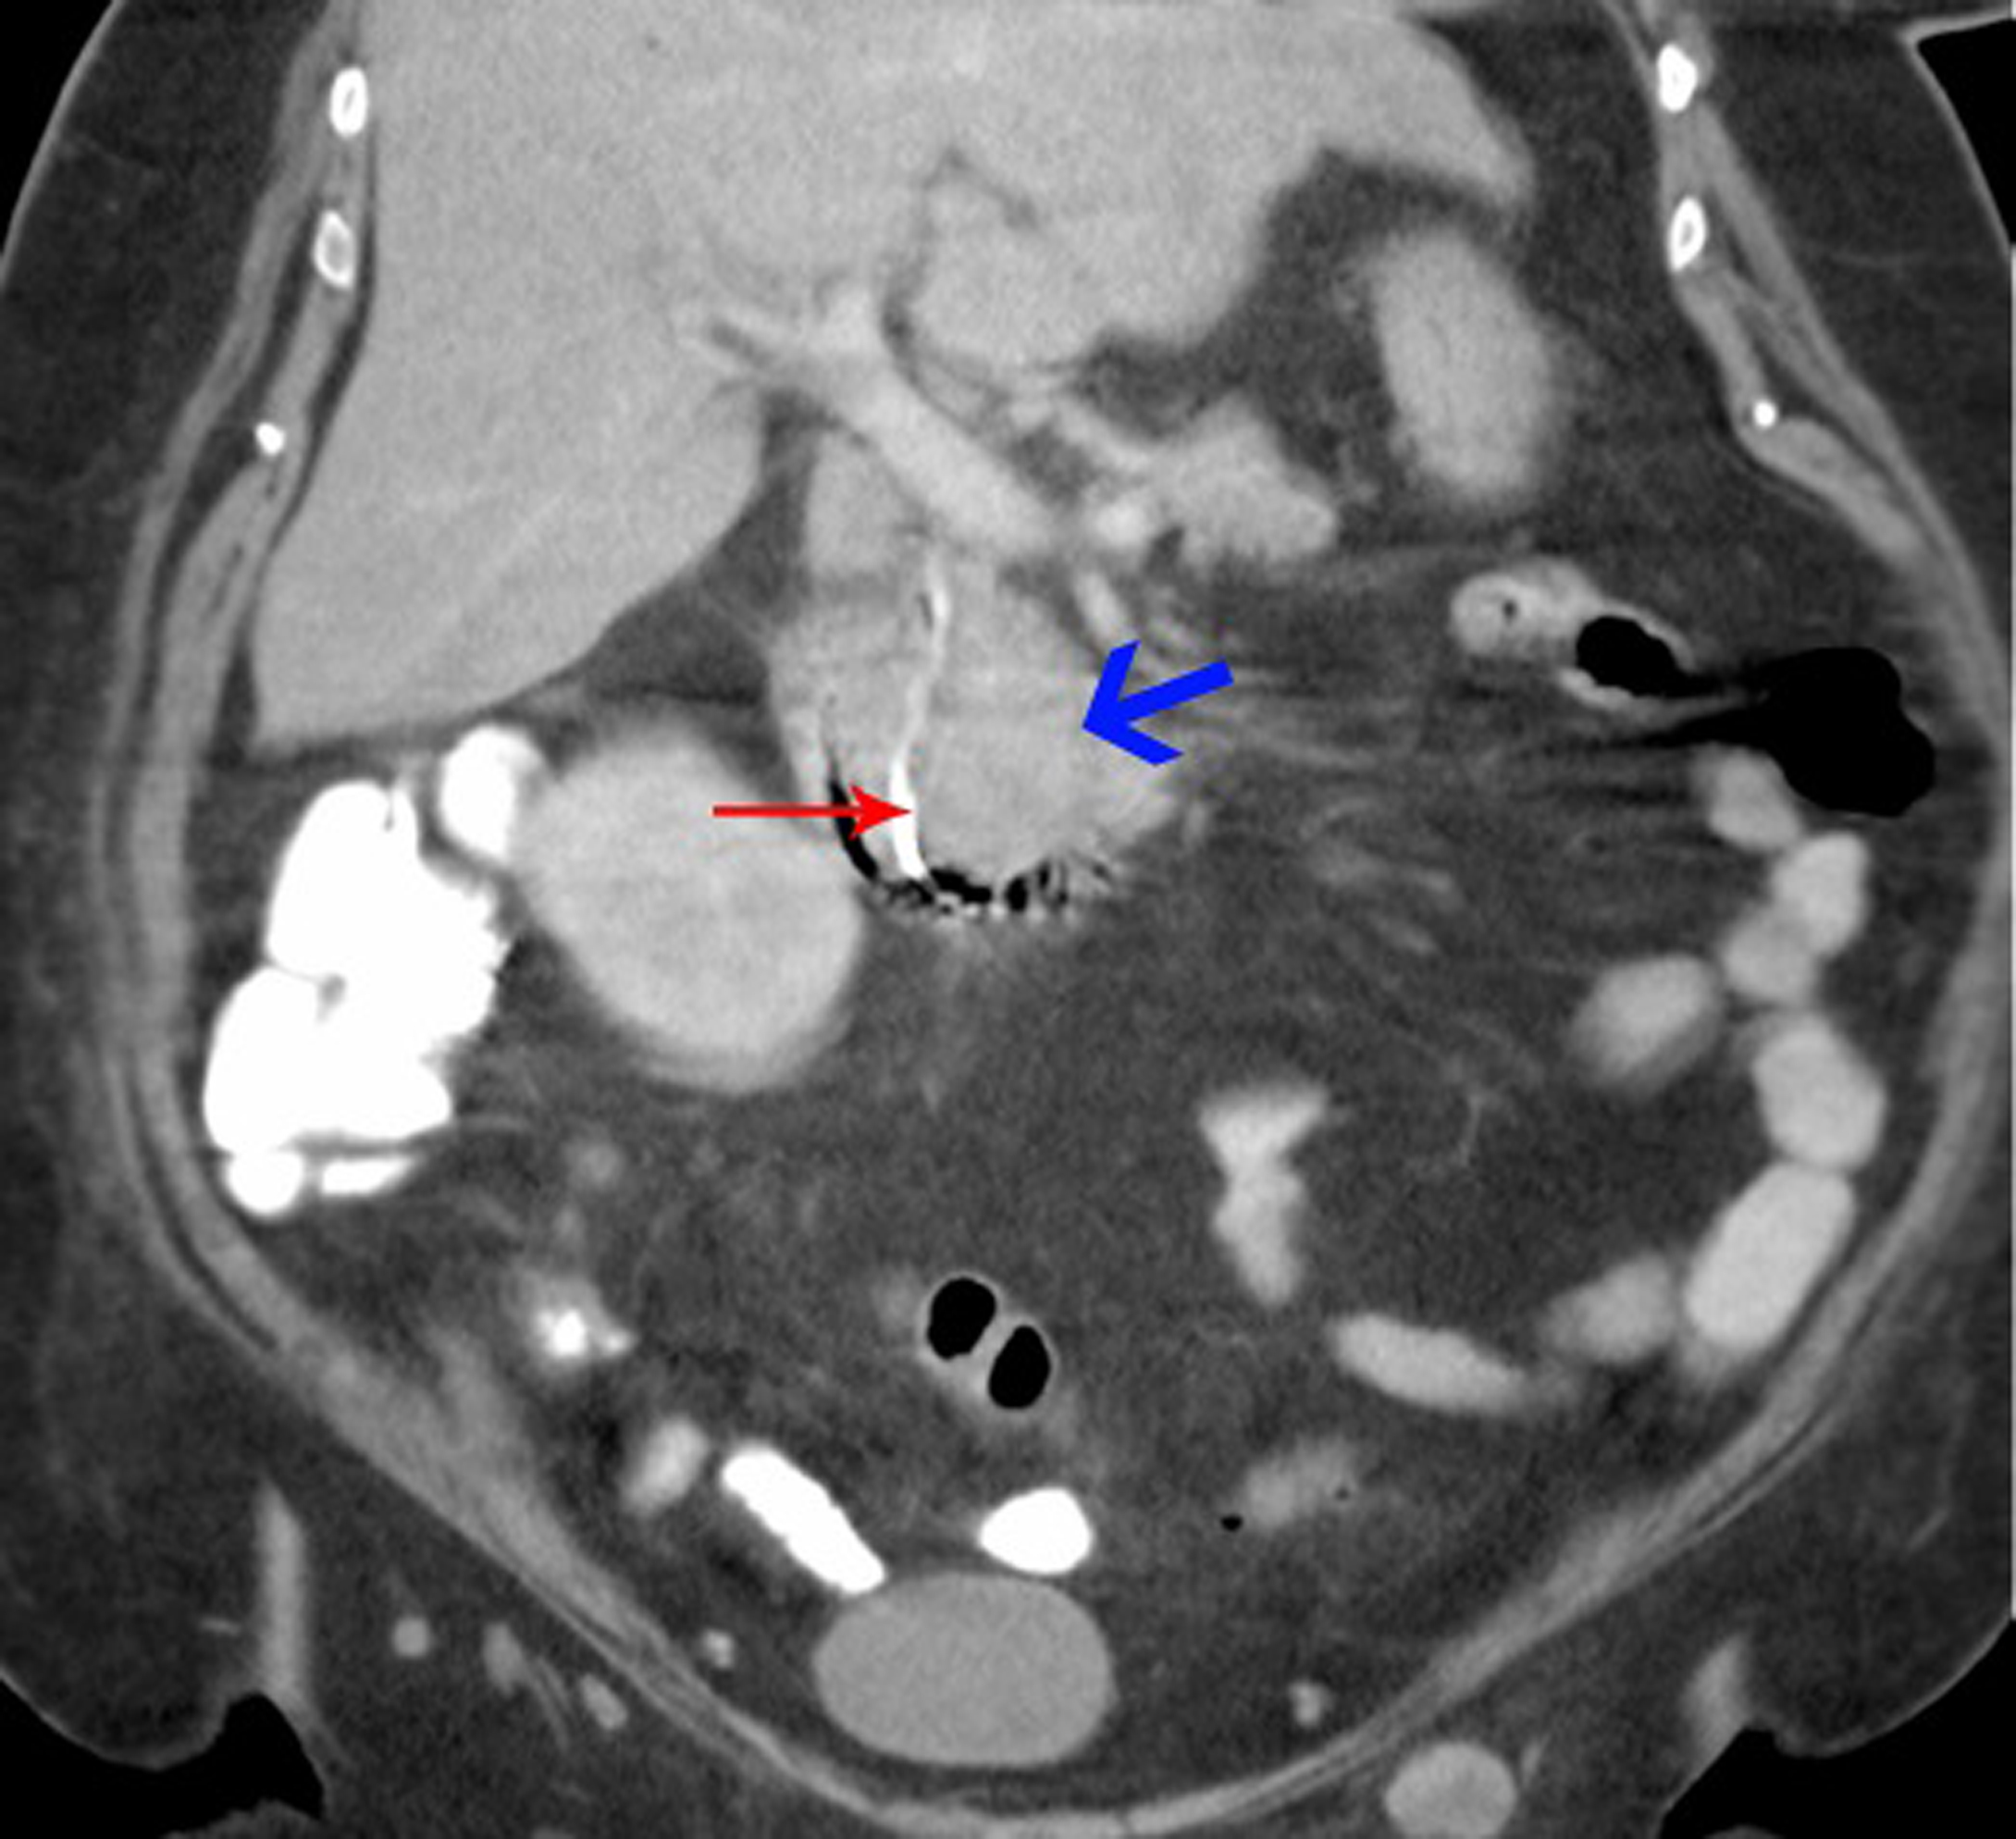

A biliary stent was inserted successfully during the endoscopic retrograde cholangiopancreaticogram (ERCP) (Fig. 2) and satisfactory drainage was achieved. Her liver enzymes and bilirubin improved significantly. A restaging CT showed a 6.0 x 4.5 cm mass involving the uncinate process of the pancreas and second part of the duodenum (Fig. 3, 4). New liver lesions were also seen.

![]() Click for large image | Figure 4. Coronal view of CT abdomen: Blue arrow - tumor deposit; red arrow - biliary stent leading into duodenum. |